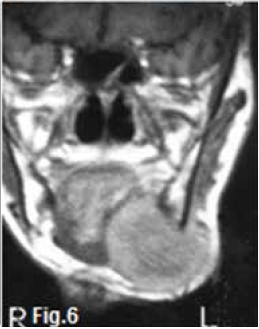

INTERPRETATION